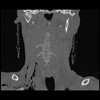

16 HUESO,,Coronal,2.000,HUESO,Coronal,